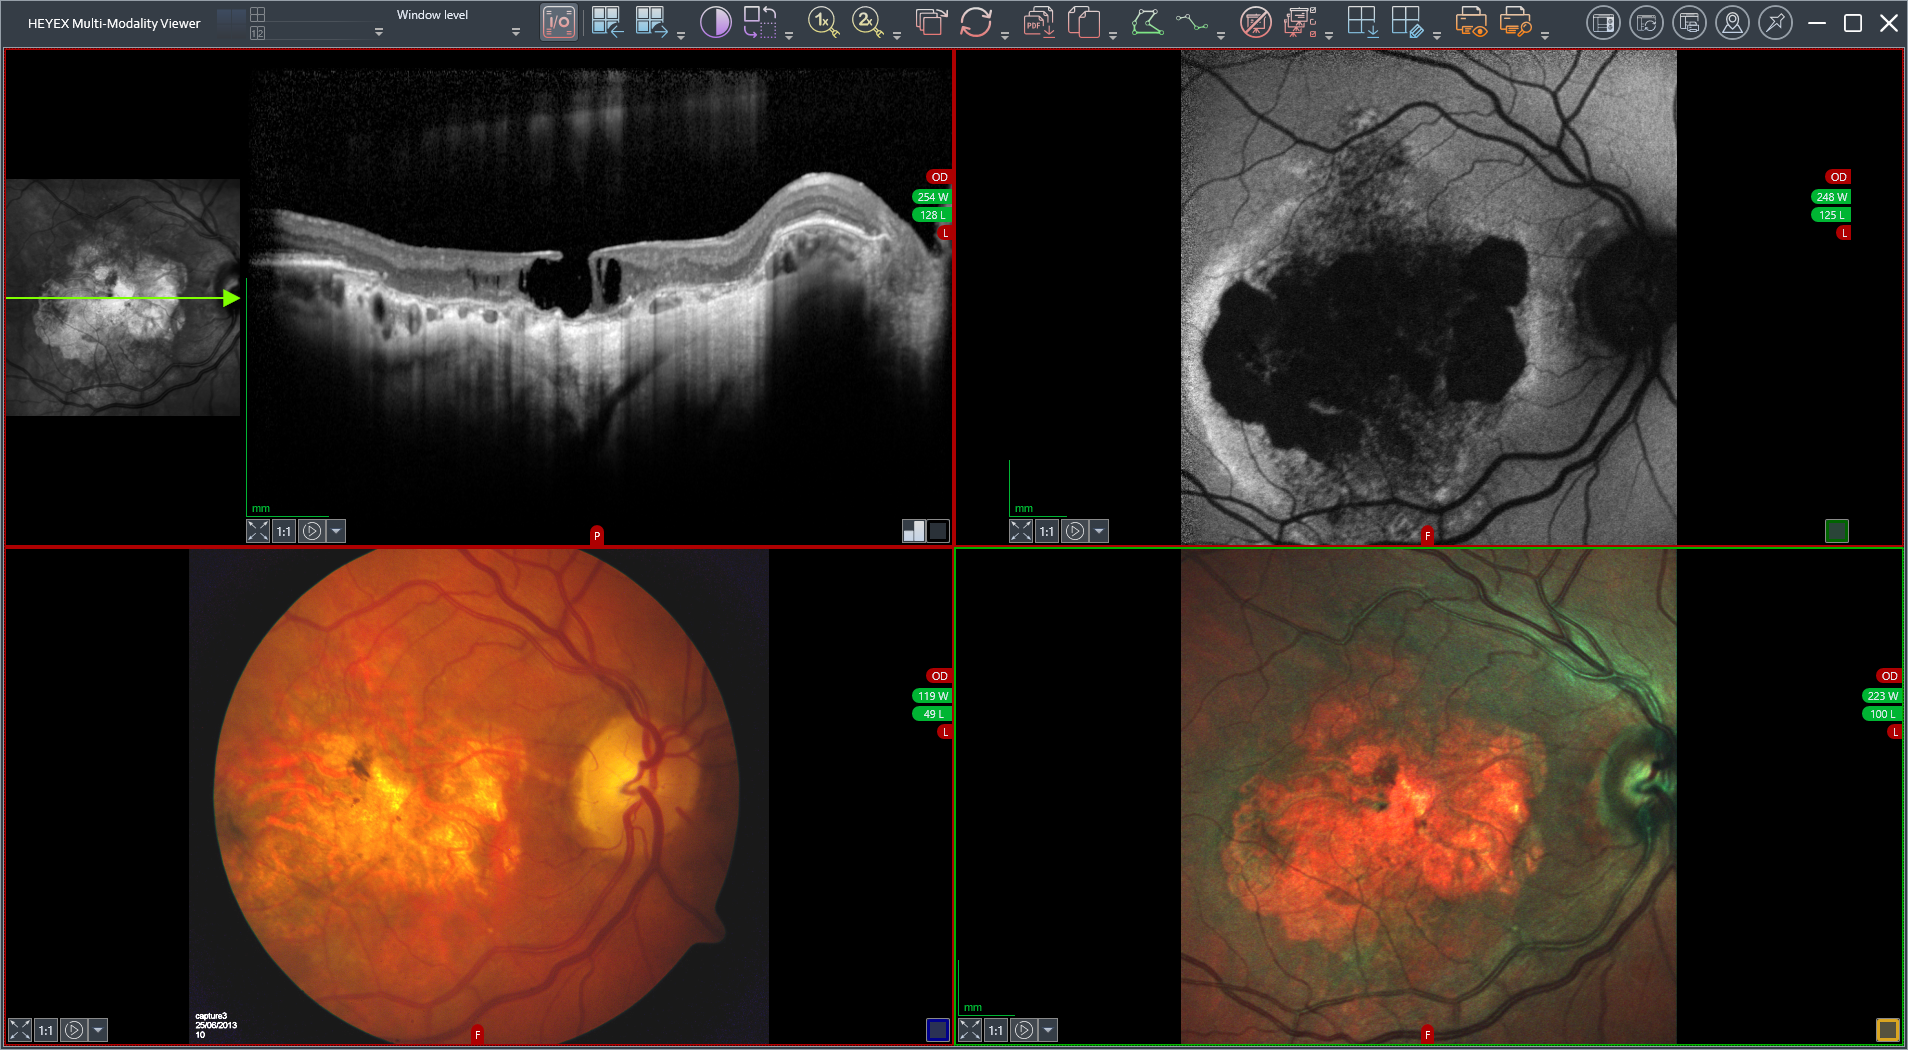

Das konfokale Laser-Ophthalmoskop (cSLO) SPECTRALIS® ist eine innovative Technologie zur Bildgebung der Netzhaut und anderer Augenstrukturen. Durch die Kombination der Selektivität von Laserlicht mit der punktgenauen Auflösung des konfokalen Scannings liefert das cSLO Bilddetails und eine Bildschärfe, die mit Fundusfotografie nicht erreicht werden können. Die cSLO-Technologie ermöglicht nicht nur die Dokumentation klinischer Befunde, sondern hebt oft auch wichtige diagnostische Details hervor, die bei der herkömmlichen klinischen Ophthalmoskopie nicht sichtbar sind. Da die cSLO-Bildgebung die Auswirkungen von Lichtstreuung minimiert, kann sie auch bei Patienten mit Medienopazitäten oder kleinen Pupillen effektiv eingesetzt werden.